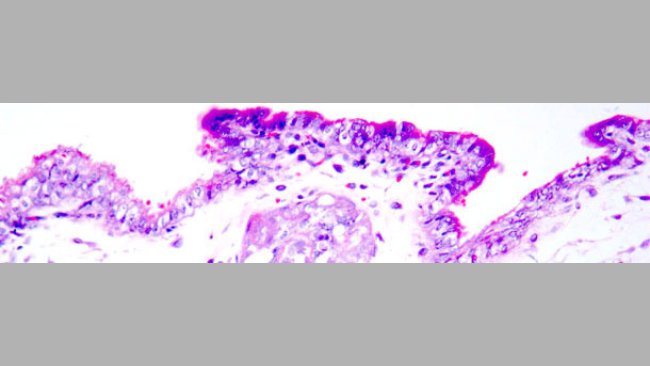

Uma das suas pesquisas actuais incide nas doenças PCV2 nos suínos. Neste tópico trabalha como patologista para suporte diagnóstico e pesquisa, sendo a mais recente dirigida para o papel da PCV2 na patologia reprodutiva suína em modelos experimentais (infecção por PCV2 em sémen exposto em porcas vacinadas e não vacinadas contra PCV2 com o objectivo de determinar fracasso reprodutivo e danos embriónicos/fetais).

A vacinação das marrãs contra a PCV2 antes da IA mostrou uma clara redução da carga viral bem como uma excreção viral muito menor, que era compatível com a protecção fetal.